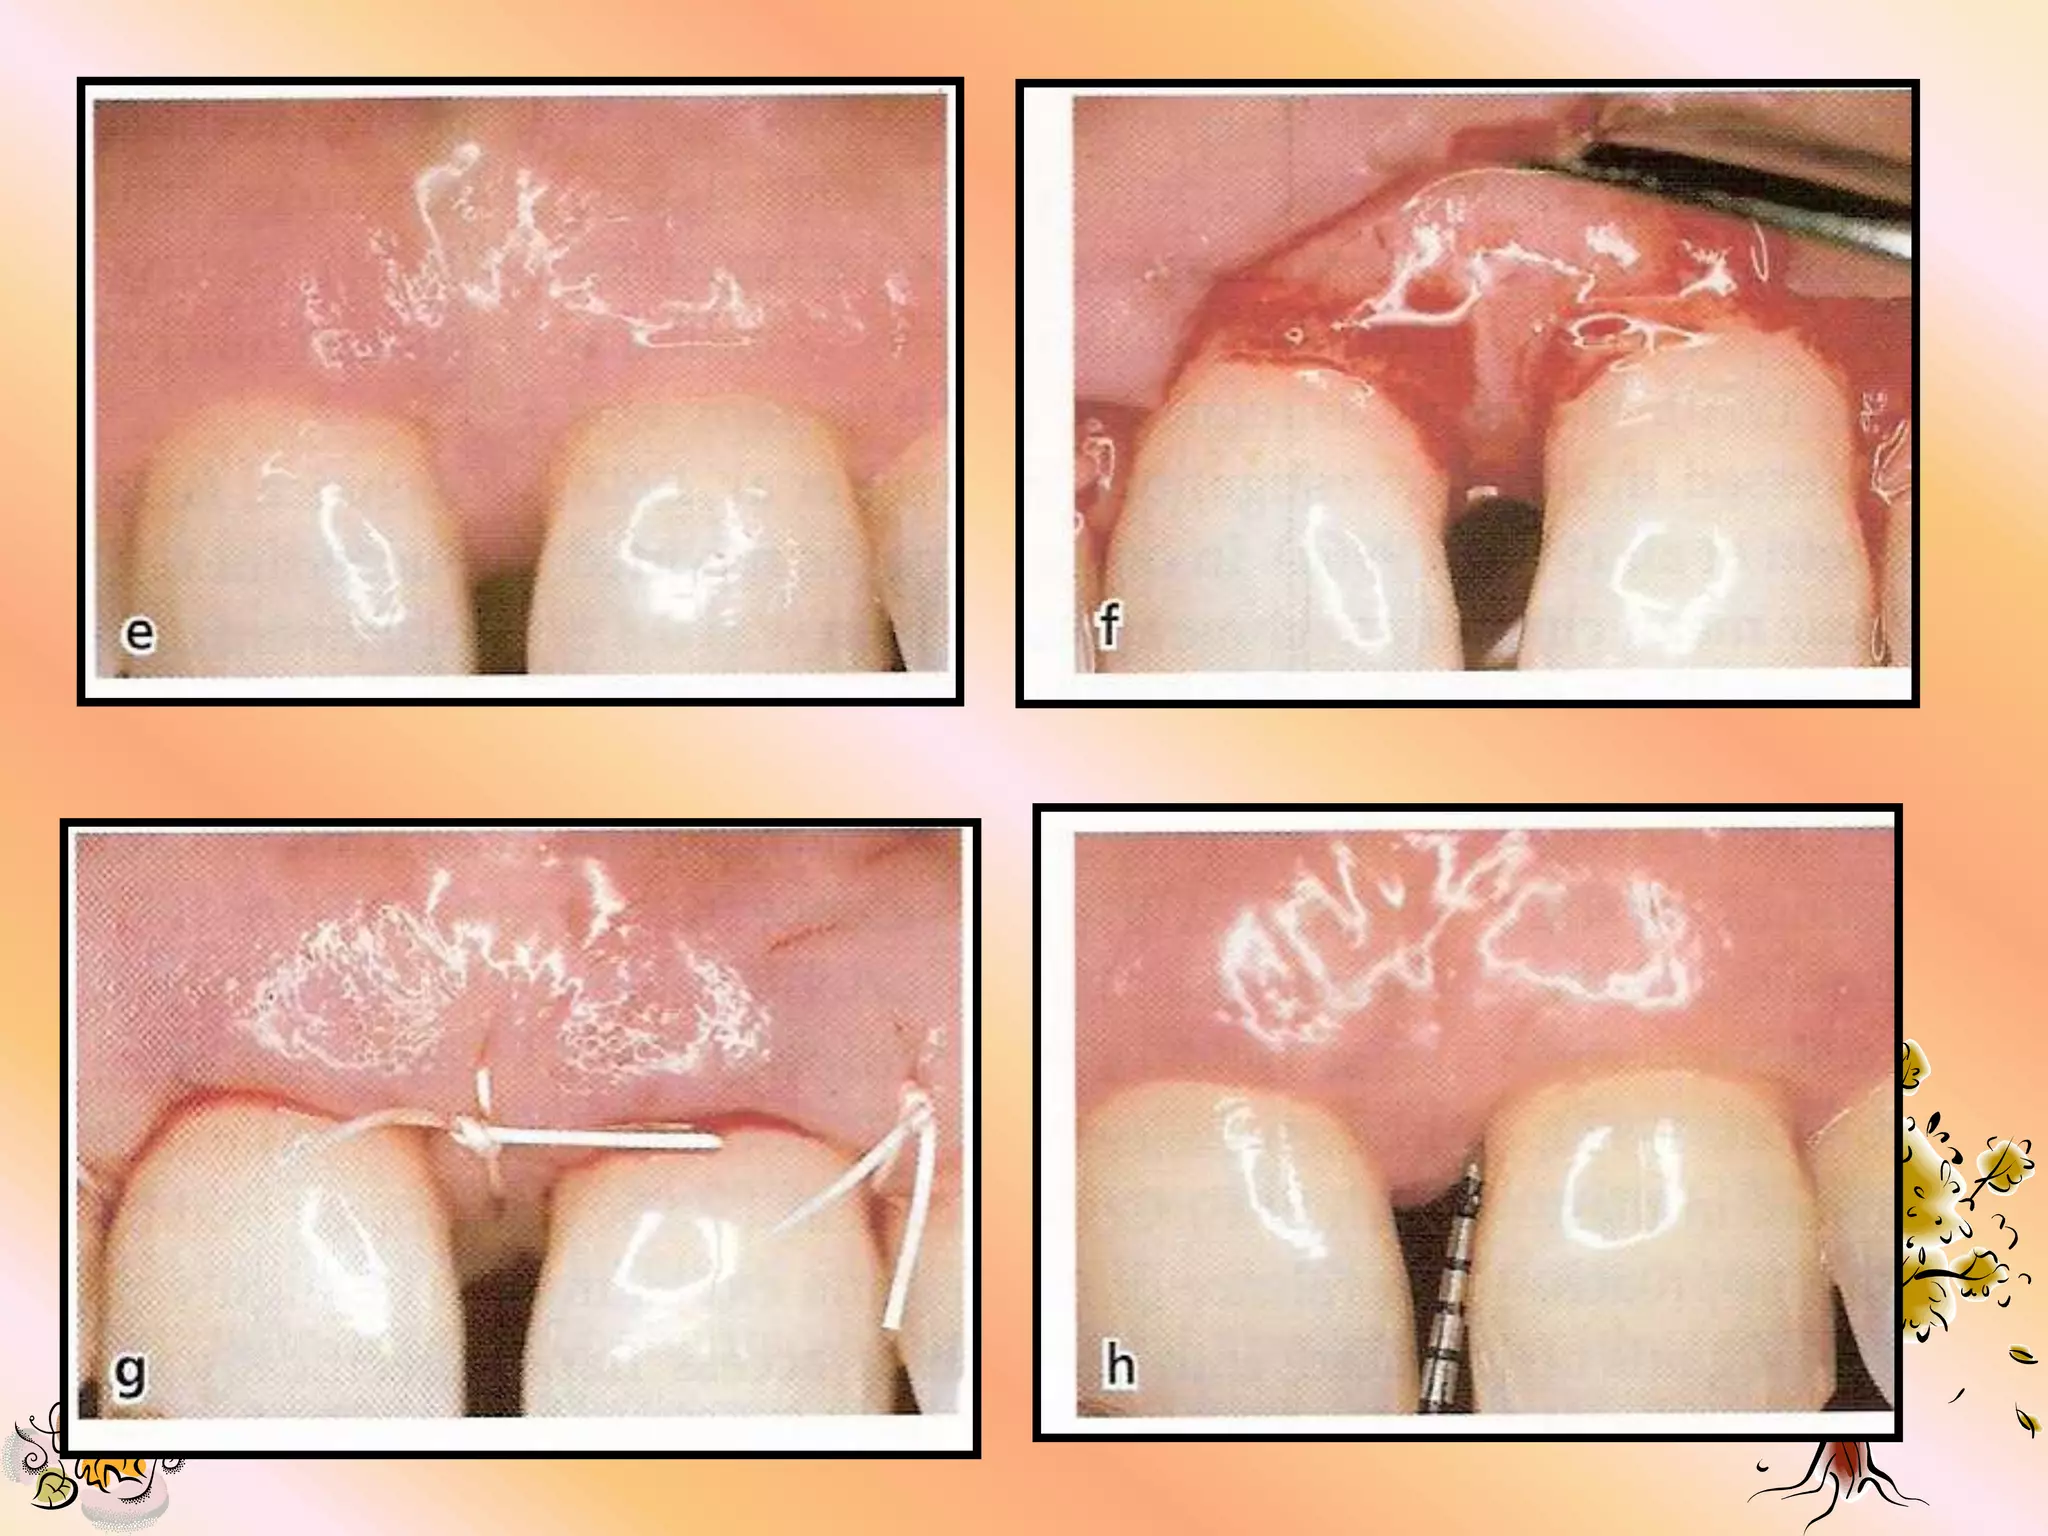

MATERIAL REMOVAL

1. Removal should

be 4 to 8 wks

after placement

or any time a

serious

complication

occurs.

2. If the material can not be removed

with a gentle tug, sharp dissection is

recommended.

3. Extreme care should be used to avoid

damaging the underlying the new granulation

tissue.

4. A small tissue forcep is used to remove the

material.

5. The flap is re-approximated over the new

tissue & sutured with silk suture.

POST OPERATIVE

CONSIDERATIONS

1.   Peridox mouth wash should be for 10 days if

the material becomes exposed, peridox

should be used untill removal.

2. Antibiotic coverage-    (7-10 days)

Tetracycline 250mg q.i.d.

Doxycycline 100mg b.i.d.

3. Use of periodontal dressing is optional.

4. Flossing at the treatment site is to be avoided

while the material is in place.

5. The patient should be seen biweekly if there is

no exposure, & wkly if exposure is present.

6. Do not attempt to cover the previously

exposed material.

7. The material should be removed immediately if

any complication develops.